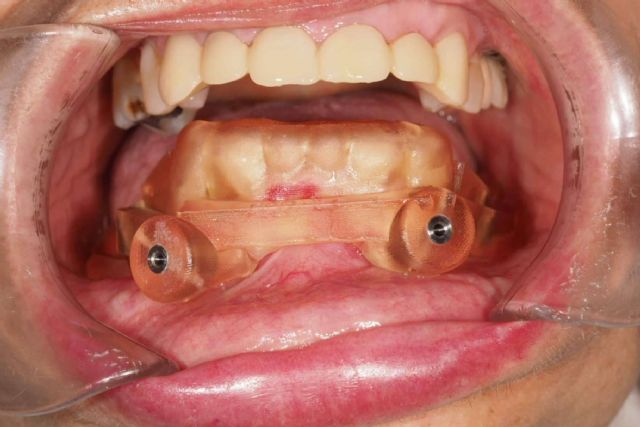

La cirugía guiada permite desde una planificación digital, garantizar la correcta ubicación de los implantes dentales en pacientes con poca cantidad de estructura ósea y a su vez poder realizar el diseño y confección de la futura prótesis que se le colocara el paciente el mismo día de la cirugía, consiguiendo que el paciente se integre más rápido a sus labores cotidianas, con mayor autoestima, una correcta función y mayor estética.

Para garantizar el éxito en sus actuaciones terapéuticas, diseñan y planifican todo el proceso quirúrgico para la colocación de implantes. De esta manera, estos tienen que encajar a la perfección con la estructura de los maxilares del paciente y, a su vez, tienen que estar en armonía con el resto de piezas dentales.